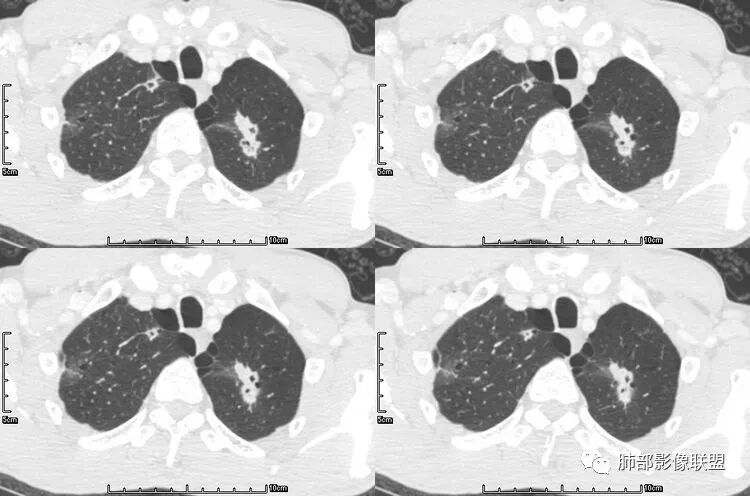

病例三

病史为结肠腺癌;双肺多发薄壁囊腔转移瘤

来源于杨凌婧.囊性空洞型肺转移瘤1例报告[J].实用医院临床杂志,2016,13(01):157-158.

空洞型肺转移瘤成因尚不完全明确, 可能与鳞癌中心角化物排空 、腺癌黏液样退变后黏液排空 、肿瘤血供不足引起坏死 、肿瘤继发脓肿 、化疗等机制有关,其中部分薄壁囊腔样结可能是肿瘤细胞沿着原有的肺大泡或其它囊性结构生长或者肿瘤向小支气管侵犯引起活瓣性阻塞而形成 ,但无一种机制能解释全部现象。空洞或囊腔大小并不反映病情变化, 其临床意义不大, 而瘤灶的数目及大小, 特别是瘤灶实性成分的多少才可能更准确反映病情变化。肺癌形成空洞与其肿瘤本身性质有明显联系,肿瘤分化程度差,倍增时间越短,恶性程度越高,组织液化坏死形成空洞倾向越明显;鳞癌空洞偏大,内缘不规则,常易形成X线平片中癌梁样改变与CT中壁结节样改变;而腺癌空洞大小不定,洞内分隔明显,内缘不规则,且较难于形成壁结节等改变;合伴空洞的肿瘤边缘情况也对判断肿瘤性质有帮助。

其中囊样空洞和小环形空洞属于薄壁空洞,泡样空洞和不规则空洞属于厚壁空洞,其中腺癌空洞型肺转移瘤主要表现为小环形空洞,以下3个病例均表现为小环形空洞的转移瘤: